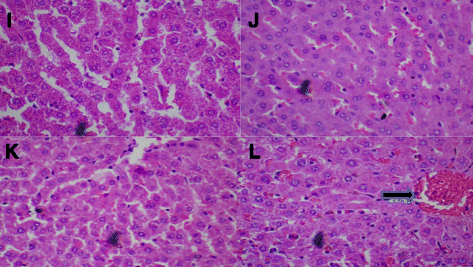

BSC(500 mg/kg):对照组(蒸馏水,10 ml/kg,I)和BSC(250 mg/kg,J,500 mg/kg,K)显示正常肝脏。但是,BSC(1000 mg/kg,L)显示肝窦和中央静脉充血(见箭头)。